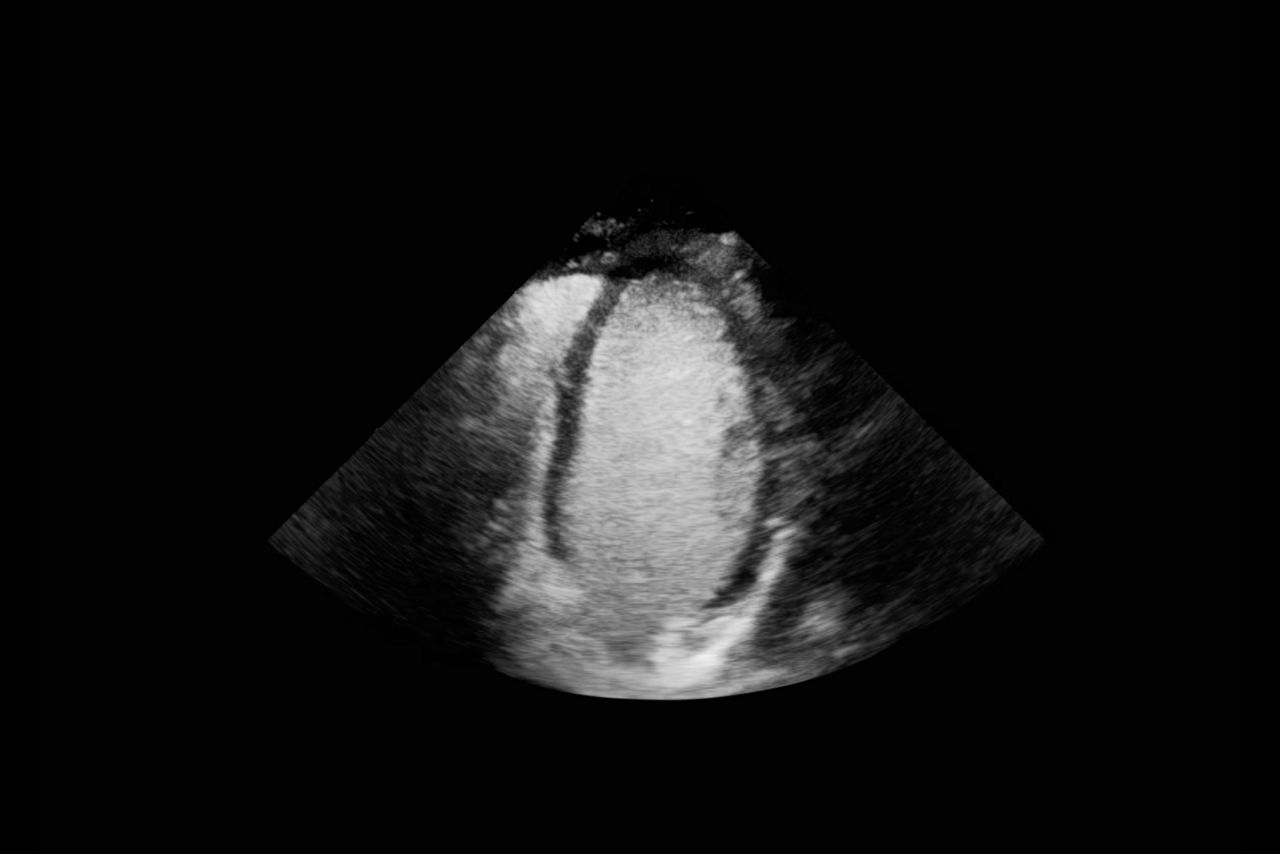

Clear delineation of the endocardial borders may help facilitate evaluation of LV wall motion and function.

a) Images obtained with Vivid™ S70 scanner using Optison.

b) While the products can be used together, Optison and Vivid™ S70 are not Combination Products per 21 CFR 3.2(e); each was FDA-approved independently and neither requires the other.